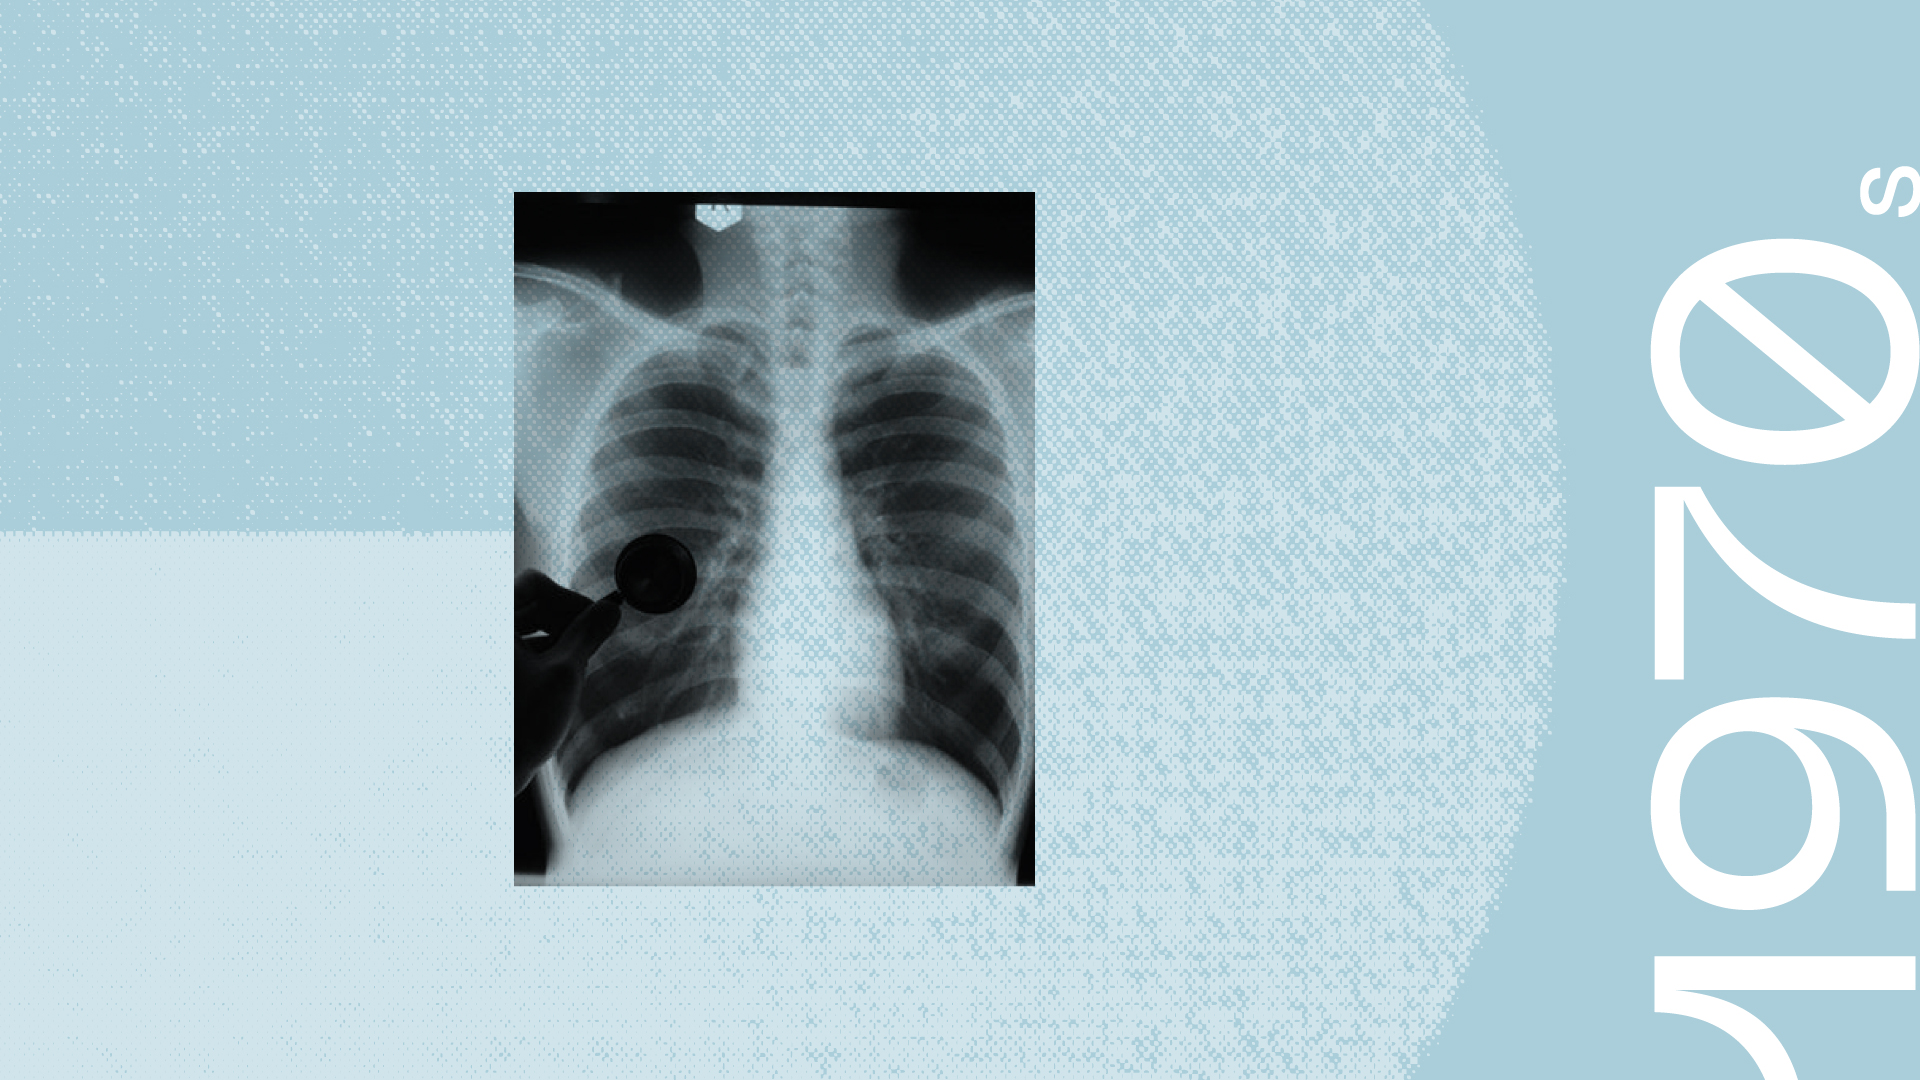

SRI researchers conducted a series of studies that modeled the pathogenesis of human respiratory diseases such as emphysema and chronic obstructive lung disease. The studies proved that these diseases were caused in humans by common contaminants of air derived from industrial and automobile exhausts and tobacco smoke. The results were fundamental to national and international efforts in setting allowable limits of nitrogen oxide and ozone contents in industrial exhausts and indoor air-quality standards.